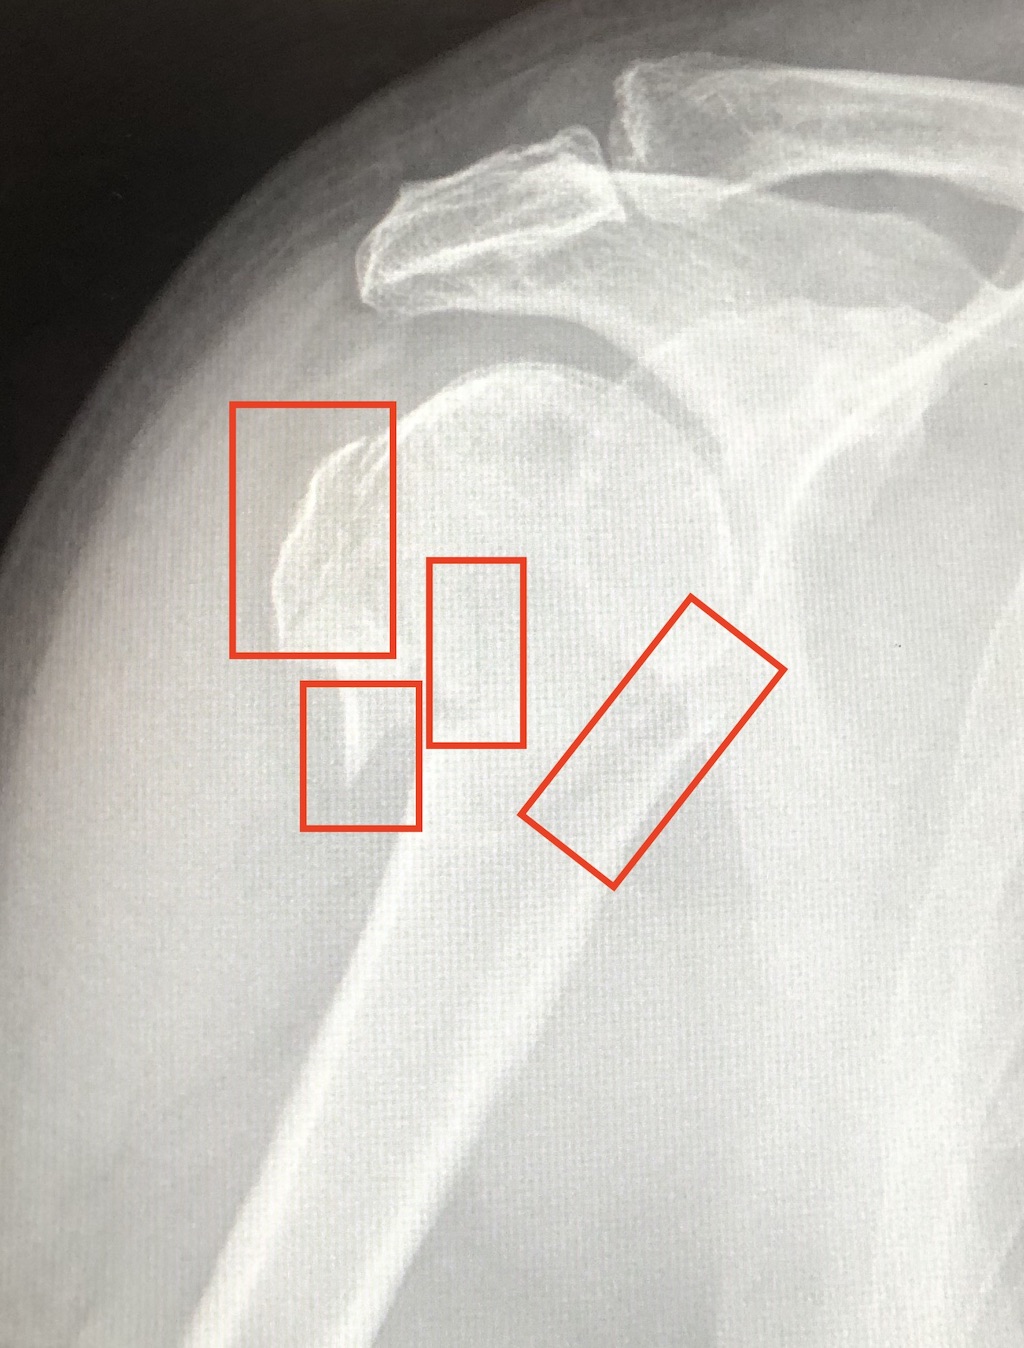

My broken arm